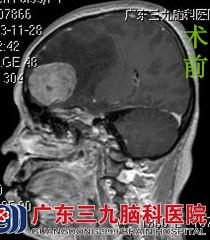

陈阿姨一家人来到广东三九脑科医院,行头颅MR检查提示右侧额部大脑镰旁示占位病变,大小约4.6cm×4.1cm×3.3cm,双侧脑室前角受压变窄,病变区域的中线结构明显向左侧偏移,鲁明主任考虑脑膜瘤可能性大。完善相关检查后,由鲁明主任主刀,在全麻下行右侧额部大脑镰旁脑膜瘤切除术,术中显微镜下见灰白色肿瘤,呈颗粒状,血供不丰富,质中,予肿瘤全切,手术顺利结束。术后经专科治疗护理,陈阿姨康复出院。术后病理结果:过渡型脑膜瘤。